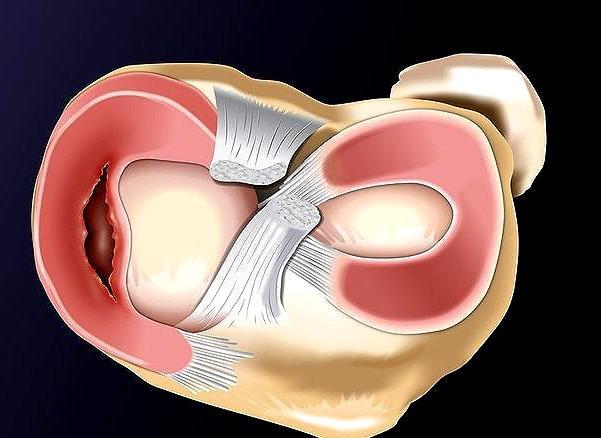

半月板是两个月牙形的纤维软骨,位于胫骨平台内侧和外侧的关节面,分别为内、外侧半月板。

Ⅲ度以上的半月板损伤需要手术,但手术不等于切除,在切除半月板之前先考虑半月板缝合。

随着医学的发展进步,针对各种半月板损伤的缝合技术在不断完善,如今大部分红区的半月板损伤都能够缝合,加上红区血运好,在缝合之后的愈合率也比较高。患者在诊断出半月板损伤后,对于轻度损伤做好保守治疗并定期复诊,对于重度损伤及时选择关节镜下缝合修复,并非一定要切除半月板。

总之,半月板损伤后要尽可能保留光滑的半月板,切除虽然简单,但切除半月板后,胫骨平台上的峰压力可上升2倍,容易引起软骨退变。当然,对于半月板结构大部分或全部消失,而且伴有严重的增生性骨关节病和软骨损伤者,评估病情后,该考虑切除半月板的还是要考虑切除。